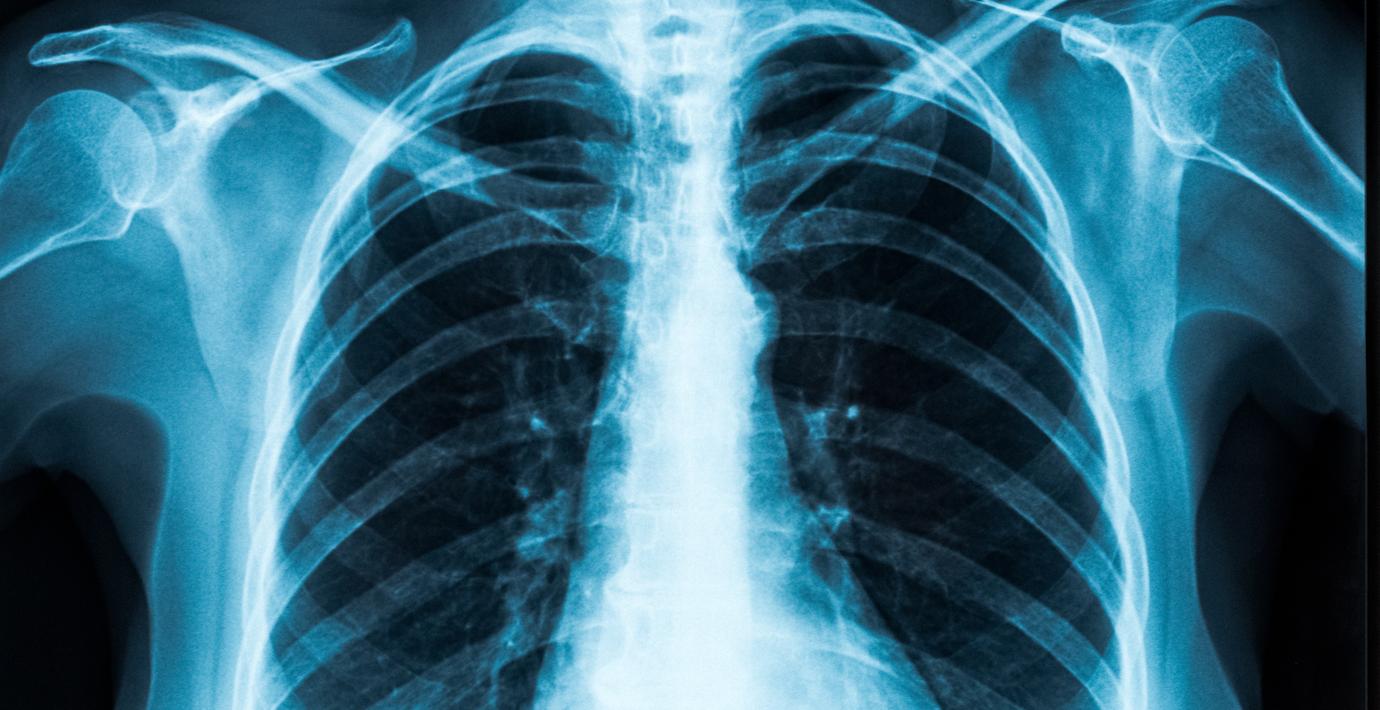

Astra Zeneca ser potential för Tagrisso i fas 3-studie

Astra Zeneca ser i resultat från Flaura 2-studien med läkemedlet Tagrisso mot en form av lungcancer i fas 3 potential för ett nytt behandlingsalternativ som uppges "bygga på fördel…